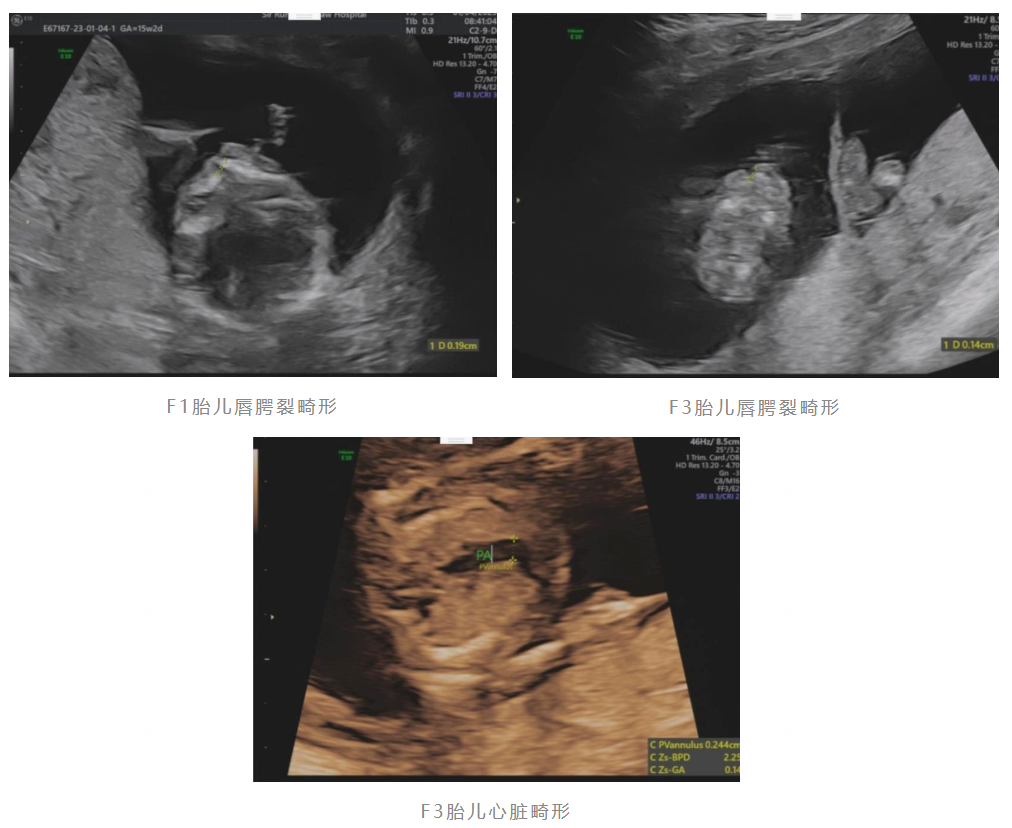

钱小小给孕妇做b超,却看见双胞胎出现这问题,医生脸色大变